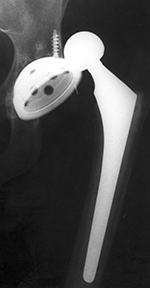

Partial Hip Replacement

There are three basic types of hip arthroplasty. Partial hip replacement or hip hemiarthroplasty replaces the femoral head and neck and leaves intact the native acetabulum. Hip hemiarthroplasty may consist of a single metallic unit, a unipolar hemiarthroplasty or endoprosthesis (figure: hip endoprosthesis). Or it may consist of a bipolar hip hemiarthroplasty in which there is replacement of the femoral head and neck and placement of a prosthetic acetabulum which is press fit into the native acetabulum. The bipolar hip prosthesis acetabulum is a polyethylene lined metal cup. It fits into a small femoral head which is locked to the attached metal femoral stem (Mulcahy, 2012). The bipolar hip hemiarthroplasty allows motion between the prosthetic femoral head and the polyethylene lined cup as well as between the cup and the native acetabulum (figure: bipolar hip prosthesis).

Because of the motion at

both interfaces, bipolar hip hemiarthroplasty

tends to be less prone to dislocation than an endoprosthesis. It also theoretically

results in less wear of the acetabular articular

cartilage that would eventually lead to pain and acetabular

protrusio (Berquist, 1995; Benjamin, 1994). There are variations on the standard bipolar hip prosthesis with claw plates or cerclage wires used to stabilize the stem of the prosthesis (figure: bipolar hemiarthroplasty with claw plate).

| Bipolar hemiarthroplasty (prosthesis) |

Bipolar hemiarthroplasty (prosthesis) |

Bipolar hemiarthroplasty (prosthesis)

| A free riding acetabular cup is press fit into the native acetabulum. The acetabular cup articulates with a prosthetic femoral head and stem component. From Benjamin, 1994 |

From Benjamin, 1994 |

92 year-old woman treated for left femoral neck fracture. From Taljanovic, 2005 |